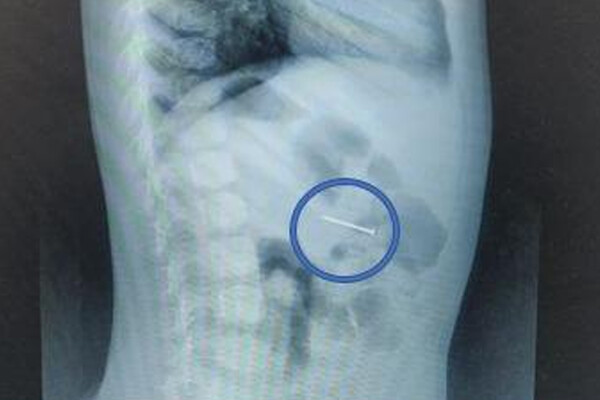

«Своевременно начатое вмешательство помогло избежать серьезных последствий. Сперва мы сделали рентгенографию – она подтвердила наличие гвоздя в желудке, а после выполнили гастроскопию: с помощью эндоскопических щипцов аккуратно захватили гвоздь за острый конец и извлекли его через ротовую полость», — поделился врач-эндоскопист Руслан Мусаев, добавив, что манипуляция заняла около 20 минут.